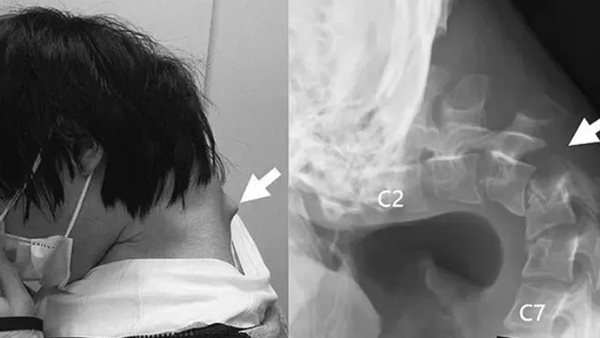

في حالة طبية نادرة ومقلقة، أُصيب شاب ياباني يبلغ من العمر 25 عامًا بـمتلازمة سقوط الرأس، بعد أن أمضى سنوات طويلة في استخدام هاتفه الذكي بشكل مفرط، ما أدى إلى ضعف شديد في عضلات رقبته وعدم قدرته على رفع رأسه.

الفحوصات الطبية كشفت عن تشوهات في فقرات الرقبة، بالإضافة إلى وجود أنسجة ندبية ناجمة عن إجهاد مستمر وطويل للعمود الفقري العلوي. حاول الأطباء في البداية تثبيت الرأس بأطواق طبية، لكن مع تزايد الأعراض مثل التنميل، لجأ الفريق الطبي إلى سلسلة من العمليات الجراحية الدقيقة، شملت إزالة جزء من الفقرات والنسيج الندبي، وتثبيت الرقبة بمسامير وقضبان معدنية.